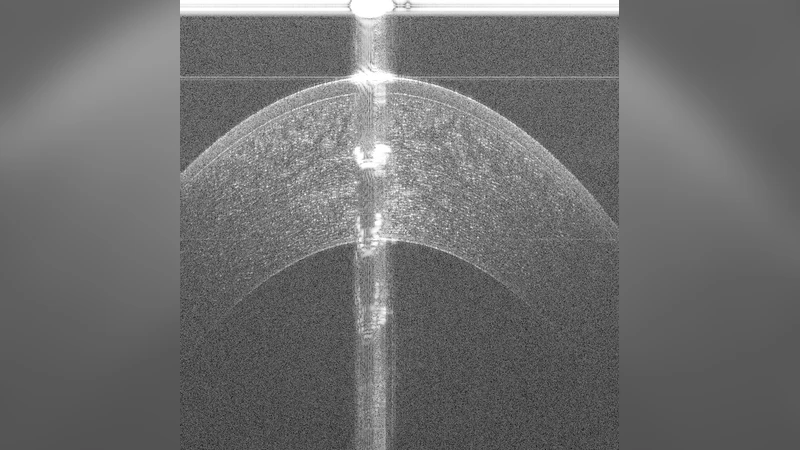

본 논문은 전방 안구 OCT B‑scan에서 얕은 조직 경계가 가려지는 강한 스펙큘러 아티팩트와 스페클 노이즈를 제거하기 위해 조건부 생성적 적대 신경망(cGAN)을 사전‑분할 단계로 적용하고, 원본 이미지와 사전‑분할 결과를 결합한 Tissue Interface Segmentation Network(TISN)으로 최종 경계를 정밀하게 추출한다. 코라놀·림벌 데이터셋에서 높은 정확도를 달성했으며, 전통적 그래프 기반 알고리즘과 결합한 하이브리드 방식에서도 성능 향상을 보였다.

이 연구는 전방 안구 OCT 영상이 안구 전면(각막, 림버)에서 흔히 나타내는 강한 스펙큘러 반사와 깊은 스페클 노이즈가 얕은 조직 인터페이스(각막 전표면, 림버 상피‑바운더리)를 가려 분석을 어렵게 만든다는 문제의식을 바탕으로 설계되었다. 기존의 레이어 경계 자동화 기법은 주로 후방 망막에 초점을 맞추어 그래프 이론, 동적 프로그래밍, 전통적인 머신러닝 등을 활용했으며, 전방에서는 아티팩트 제거가 선행되지 않으면 높은 오차를 보였다. 논문은 두 단계의 연속 신경망 구조를 제안한다. 첫 번째 단계인 cGAN은 입력 B‑scan을 조건부 생성 모델에 넣어 “클린” 마스크를 생성한다. 여기서 생성자는 U‑Net 형태의 인코더‑디코더 구조에 스킵 연결을 유지하고, L1 손실과 판별기의 adversarial loss를 동시에 최소화한다. 판별기는 실제 전처리된 라벨(전문가가 만든 스펙큘러‑제거 마스크)과 생성된 마스크를 구분하도록 학습한다. 이 과정은 스펙큘러 하이라이트와 상위 스페클을 억제하면서도 실제 조직 경계 근처의 구조적 정보를 보존한다. 두 번째 단계인 TISN은 원본 OCT 이미지와 cGAN이 만든 사전‑분할 마스크를 2채널 입력으로 받아, 다중 스케일 컨볼루션과 dilated convolution을 결합한 U‑Net‑like 아키텍처로 얕은 인터페이스를 픽셀 수준에서 세분화한다. TISN은 Dice loss와 경계 정밀도를 동시에 최적화하도록 설계돼, 얇은 전표면의 미세 변화를 감지한다.